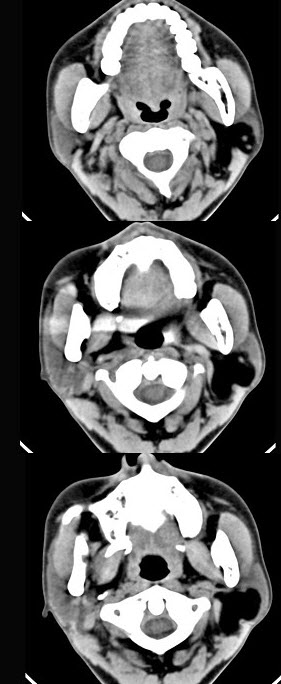

男性38岁,左侧腮腺渐进性肿大一年,无压痛,CT扫描如图所示,请选择正确的描述和结论()。

A、左侧腮腺区见低密度肿块,CT值约为-200Hu

B、肿块边缘清楚,未见邻近结构受侵

C、考虑为囊肿

D、考虑为脂肪瘤

E、考虑为血管瘤

A,B,D